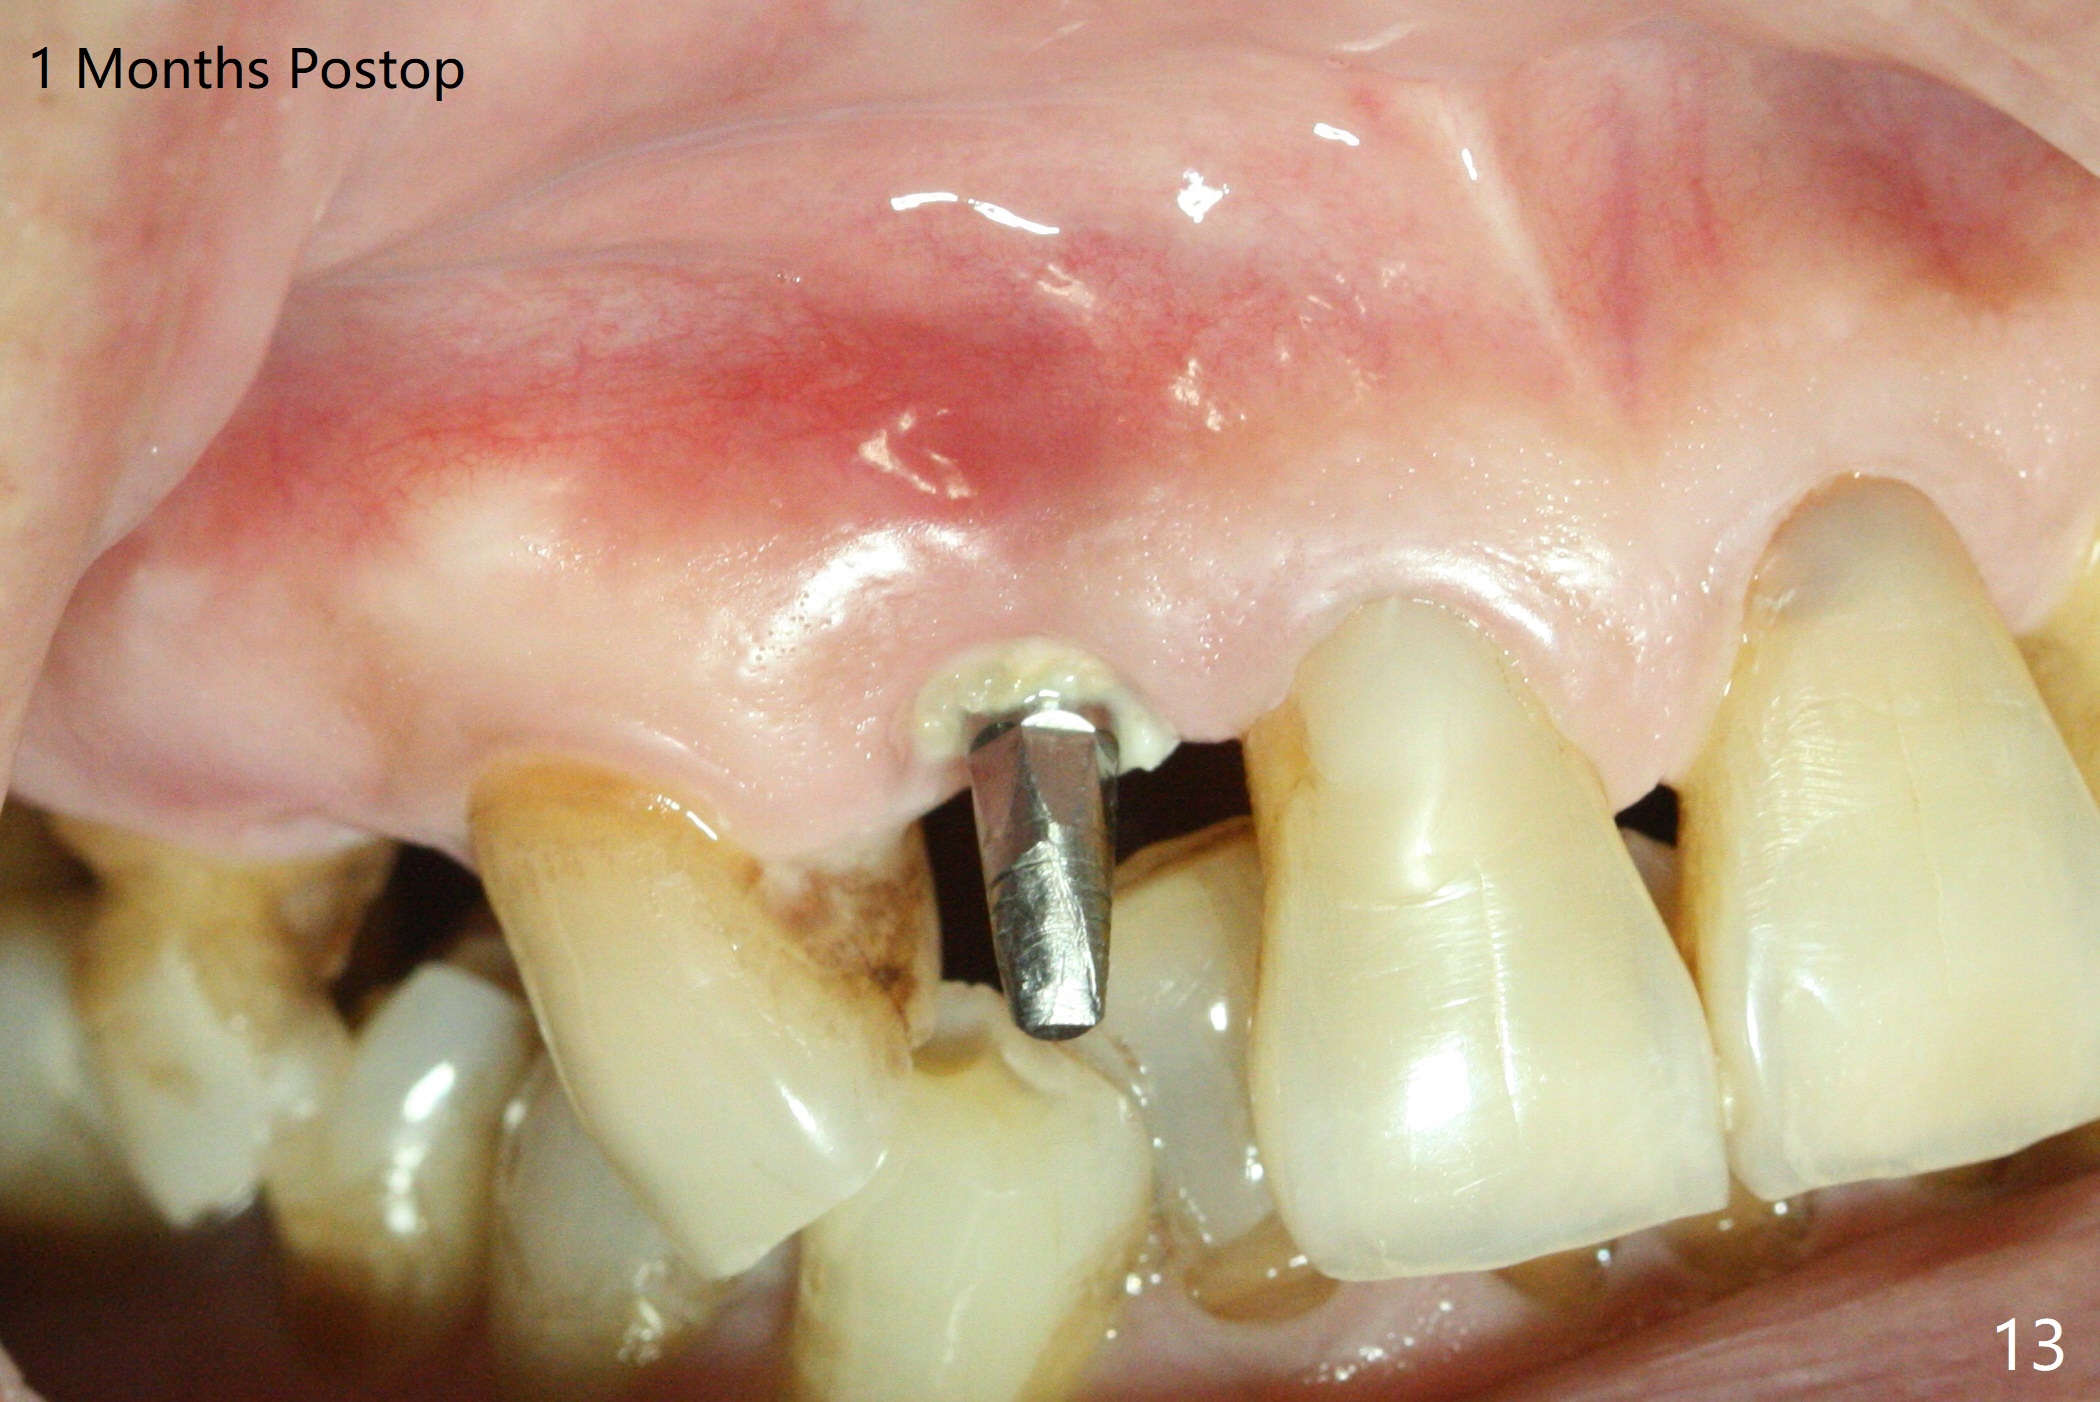

An apical abscess is present when the patient returns for immediate implant at #7 (Fig.1 *); a 2nd challenge is deep bite. After smooth extraction, the apical buccal plate is found to be perforated. Following debridement, a piece of gauze is placed in the apical defect for hemostasis, while osteotomy is initiated palatal (Fig.2). The apical defect seems to be extensive (Fig.3 yellow dashed line). A new trajectory is intended (red arrow) without much success. Before implant placement, bone graft is placed in the apical defect defect area, while a drill (Fig.4 D) is inserted in the finished osteotomy (Fig.5 O). In spite of seemingly large apical defect, the buccal crest bone exists (Fig.4 x). A 3x14(2) mm 1-piece implant is placed with stability; the first round of bone graft is apparently around the apical portion of the implant (Fig.6 *). The coronal end of the implant has to be adjusted several times buccopalatally to accommodate the deep bite. A 2nd round of bone graft following an immediate provisional closes the coronal space of the socket (Fig.7 *). CT will be taken to show the bone graft to repair the buccal plate defect when the patient returns for postop follow-up. In fact the defect is minimal in CT a month ago. The fistula does not disappear 1 week postop, but it is non tender (Fig.8). The patient complains of asymptomatic swelling in the right nostril. CT shows that the large buccal perforation is repaired with large amount of bone graft (Fig.9,10 *). It would be nicer to place the implant slightly more buccal apically (Fig.11 red lines; Fig.12 (preop design)). The buccoapical fistula disappears nearly 1 month postop (Fig.13). The apparently "lifeless" bone graft seems to be harmonious with the surrounding tissue (Fig.14). The periimplant gap reopens with implant mobility nearly 4 months postop (Fig.15), which is related to micro-movement associated with the immediate provisional. The latter is removed. A larger 2-piece implant will be placed in a 2-staged manner if needed (Fig.16). In fact the 3x14 mm straight 1-piece implant (Fig.17) has no mobility when it is retightened, but the trajectory remains buccal. Incision shows that there is no implant thread exposure. A 3x14 mm 15 degree angled 1-piece dummy implant is able to establish the correct trajectory, but there is no occlusal clearance (Fig.18). Micromovement during osteointegration may recreate loosening. Finally using Lindamann bur, the osteotomy is changed so that a 3.5x13 mm 2-piece implant does not need an angled abutment to establish occlusion (Fig.19). There is one palatal thread exposure. Allograft is placed circumferentially, followed by Human Amnion-Chorion Allograft and Collagen Plug. The wound does not heal 8 days postop (Fig.20), as related to the age (79 years old)? The wound appears to heal with a membrane on the surface (Amnion-Chorion one?) 3 weeks postop (Fig.21). The ridge looks wide 3.5 months postop (Fig.22,23). A 4.5x5.5(3) mm appears to be seated incompletely with a gap between the abutment and the implant (Fig.24<). A provisional is fabricated after heavy palatal reduction. Two months later, the provisional fractures. After repositioning the abutment with complete seating and torque (Fig.25), impression is taken. Although the buccal plate is concave, the gingiva remains healthy 10 months post cementation (Fig.26,27).